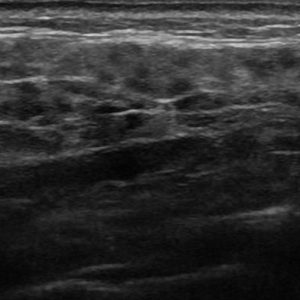

Viêm tuyến nước bọt

Lượt xem: 168» 16-01-2021 -

Viêm tuyến nước bọt

Lượt xem: 173» 16-01-2021